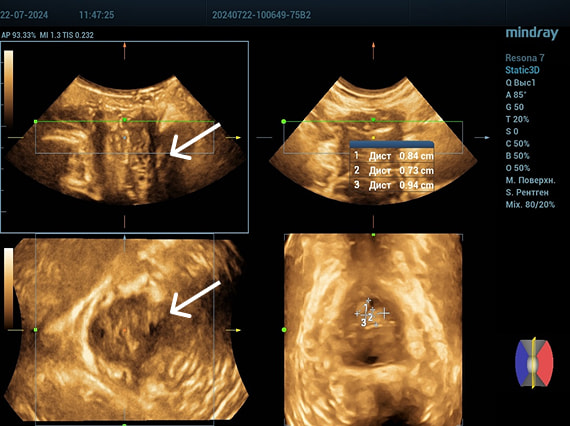

Эхограммы периуретральной области

Трансперинеальный доступ, линейный датчик.

Слева от уретры округлое образование с четкой капсулой и мелкодисперсной взвесью размерами 1,5×1,0 см (филлер с воспалением), справа — анэхогенное овоидное образование (филлер).

Эхограмма 1

Эхограмма 2

Трансперинеальный доступ, конвексный датчик.

Эхограмма 3